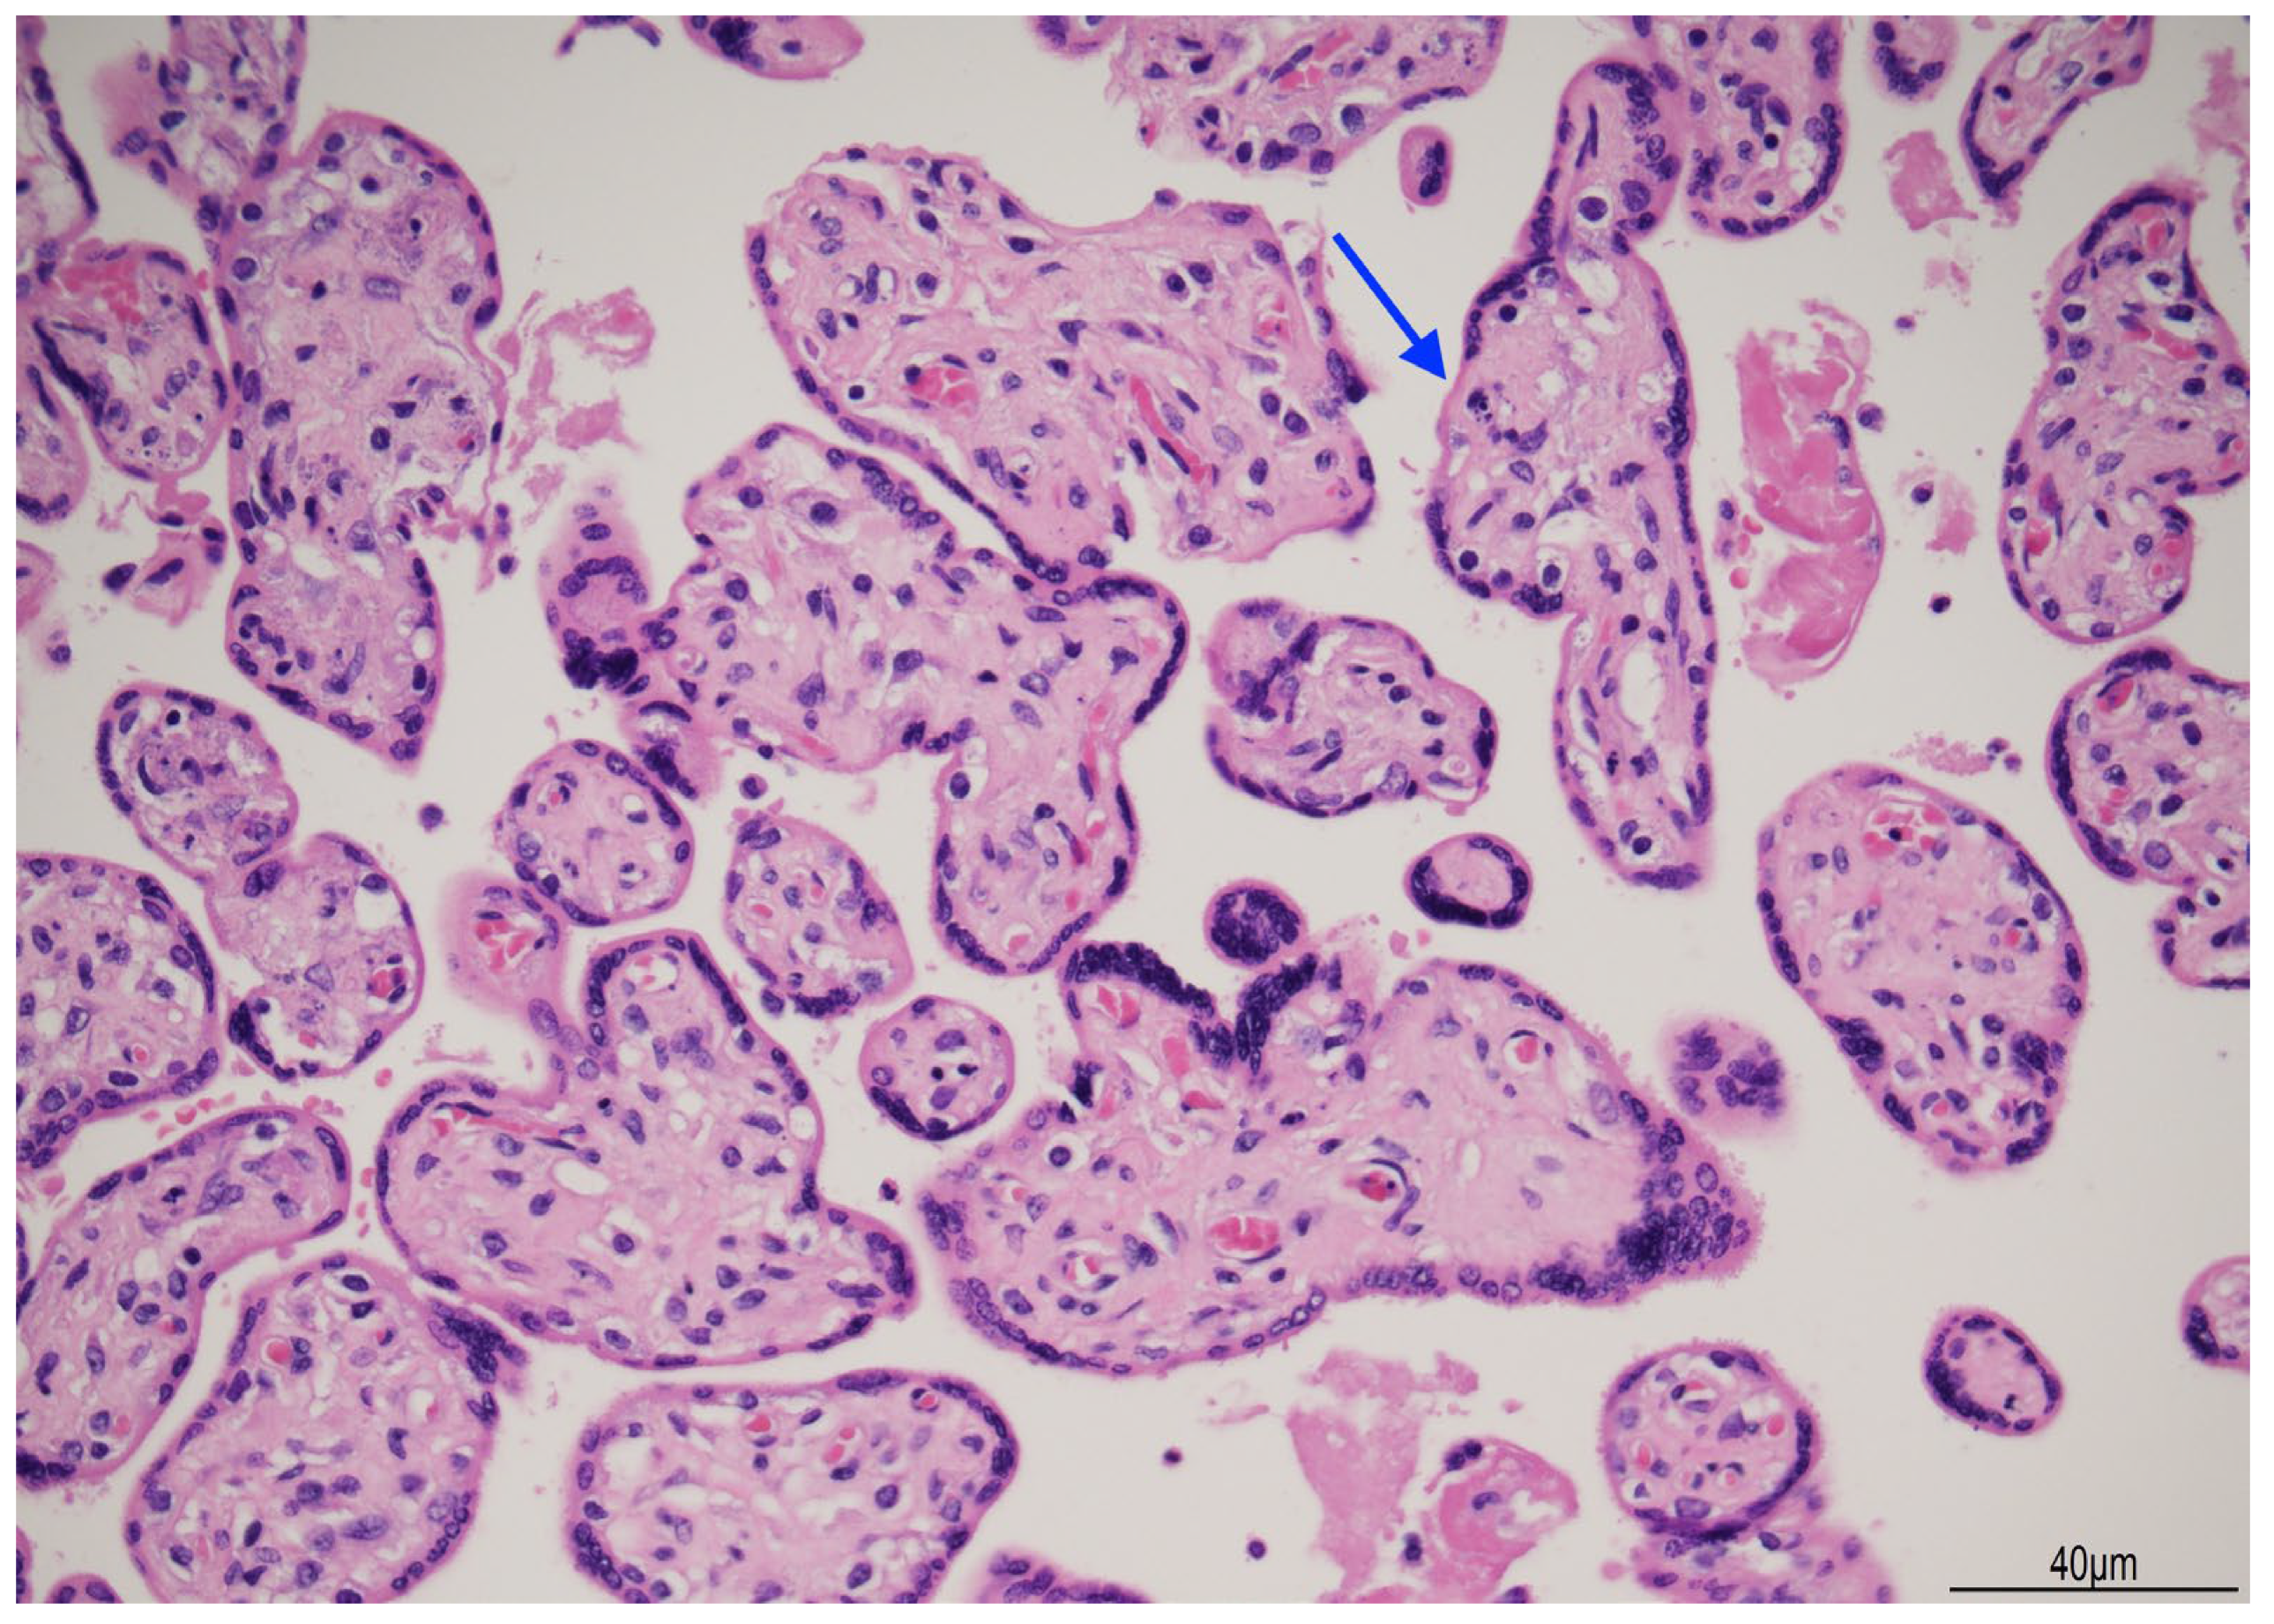

2.3. Placental Examination

3.1. The Cause of Fetal Death